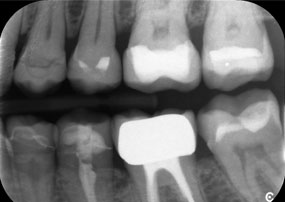

Otro ejemplo del rendimiento clínico de Power Edition fue la sustitución de una corona de zirconio dañada en una paciente de 63 años. El daño se produjo debido a la rotura de una parte del revestimiento de la corona de zirconio de 20 años de antigüedad en el diente 6. A pesar de encontrarse en la zona posterior, a la paciente le molestaba y deseaba una nueva corona.

La

El